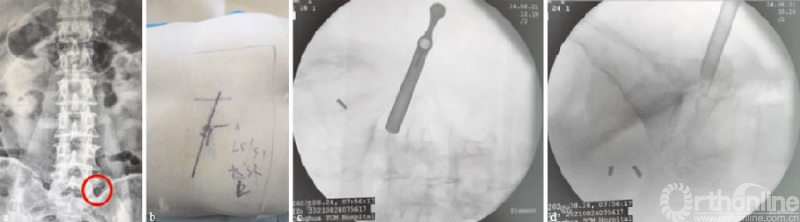

向上游离的腰椎间盘突出症由于没有上关节突的阻挡,一般通过水平穿刺或向上稍倾斜角度的穿刺,不需要行关节突成形,利用工作套管的活动度及带角度的髓核钳,可相对容易摘除椎间盘(见图4a-d);而对于向下游离的腰椎间盘突出症,要根据游离物的大小及方向,来行适当的关节突成形以扩大偏下方的椎间孔区,以顺利摘除椎间盘,减少残留可能(见图4e-h)。

(a)(b)L4/5节段向上游离型突出穿刺置管透视图,其中(a-b)为一级导杆定位图;(c)(d)工作通道放置图;(e-h)L4/5节段向下游离型突出穿刺置管透视图,其中(e-f)为保护套管下环锯行FP图;(g)(h)工作通道放置图

图4 L4/5节段游离型突出穿刺置管图

L4/5、L5S1节段突出作为最常见的腰椎间盘突出类型,其经皮椎间孔镜椎间盘切除术的开展,为保护套下环锯、可视环锯、骨钻、镜下磨钻等多样的成形技术创新提供了实践条件。在L4/5和L5S1节段,通常由于上关节突的阻挡,且Kambin's三角相对狭窄,一般在中线旁开12~14cm选择穿刺点,大部分腰椎间盘突出症患者需行关节突成形(见图4);在L5S1节段,由于椎间孔高度最小,冠状位的关节突常有高髂棘、大横突等解剖特异性存在,行经皮椎间孔镜椎间盘切除术较其他节段难度相对较大[29]

在L4/5节段,可利用腰桥扩大椎间孔,同时使该椎间隙方向与地面垂直,采用TESSYS穿刺技术适当行关节突成形则较易完成管道置入。在L5S1节段,穿刺点选择和角度要综合此节段的骨性解剖结构,勿太靠内侧及大角度穿刺,而后行关节突成形切除S1部分上关节突骨质以扩大椎间孔并顺利置入工作通道(见图6)。由于L5S1椎板间隙相对较宽,如非极外侧型腰椎间盘突出,目前多选用椎板间入路来摘除突出的椎间盘,以降低技术难度[30]

(a)(b)L5S1穿刺置管透视图,其中(a-b)为穿刺导针定位图,(c)(d)保护套管下环锯行FP图;图中可见L5S1阶段椎间孔相对狭小,且有高髂棘、大横突存在

图6 L5S1节段椎间盘突出穿刺置管图